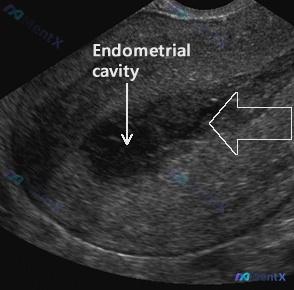

整理了一个挺有警示意义的急诊产科病例,整个分析路径很有讨论价值—— 病例基本情况 - 患者:28岁初产妇,孕10周 - 主诉:阴道出血、血栓伴痉挛1天 - 查体:生命体征尚平稳(T98.6°F,P92次/分,BP126/82mmHg,SPO298%),下腹部/骨盆压痛,阴道穹窿/宫颈口开放、有血液...